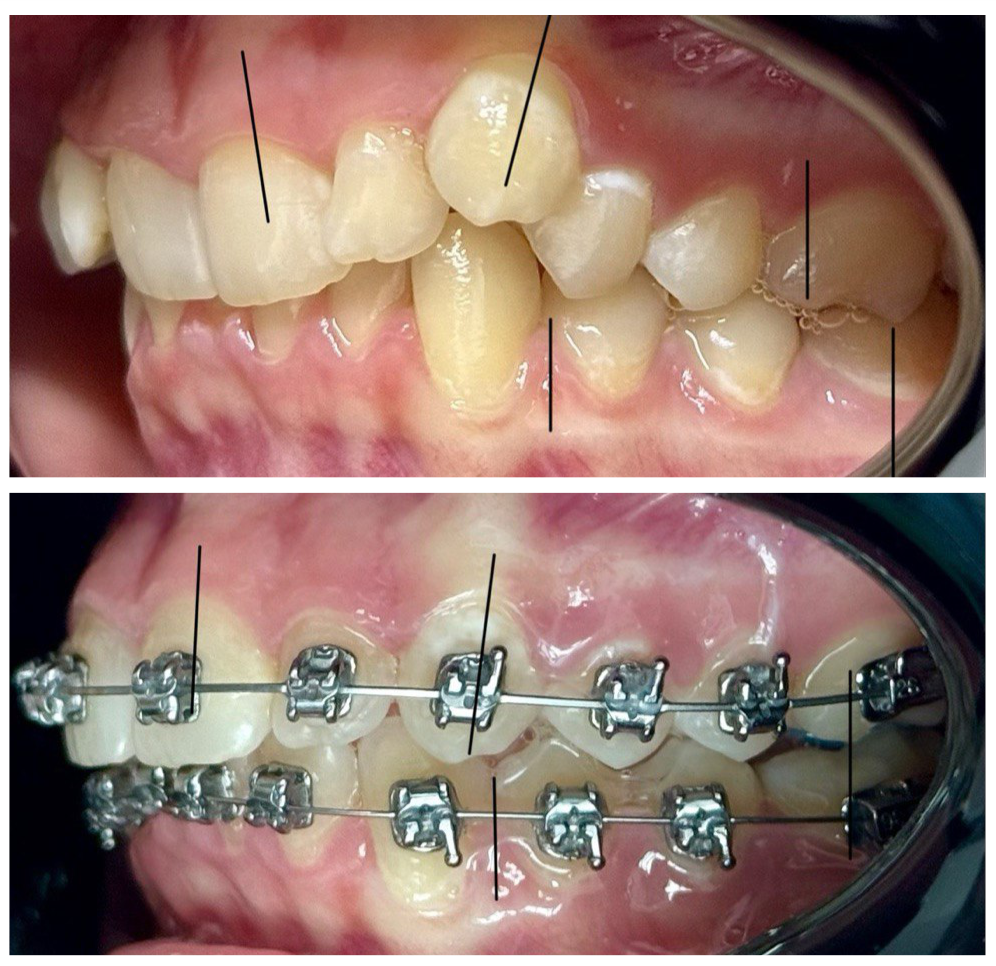

ORTODONCJA

Ortodoncja to dziedzina stomatologii zajmująca się diagnozowaniem oraz leczeniem wad zgryzu i nieprawidłowego ustawienia zębów. Leczenie ortodontyczne pozwala nie tylko poprawić estetykę uśmiechu, ale również zadbać o zdrowie całej jamy ustnej i prawidłową funkcję żucia.

Doświadczony ortodonta dobiera odpowiednie rozwiązania, takie jak aparat ortodontyczny stały lub ruchomy, a także nowoczesne, niemal niewidoczne nakładki. Prostowanie zębów i korekcja zgryzu przebiegają w oparciu o indywidualny plan leczenia ortodontycznego, dostosowany do potrzeb każdego pacjenta.

Aparaty ortodontyczne skutecznie pomagają w wyrównaniu zębów, poprawie ich ustawienia oraz eliminacji problemów związanych z wadami zgryzu. Dzięki temu leczenie ortodontyczne wpływa nie tylko na wygląd, ale także na komfort życia i zdrowie.

Jeśli interesuje Cię ortodoncja, profesjonalny ortodonta pomoże dobrać najlepszą metodę na prostowanie zębów i skuteczną korekcję zgryzu.